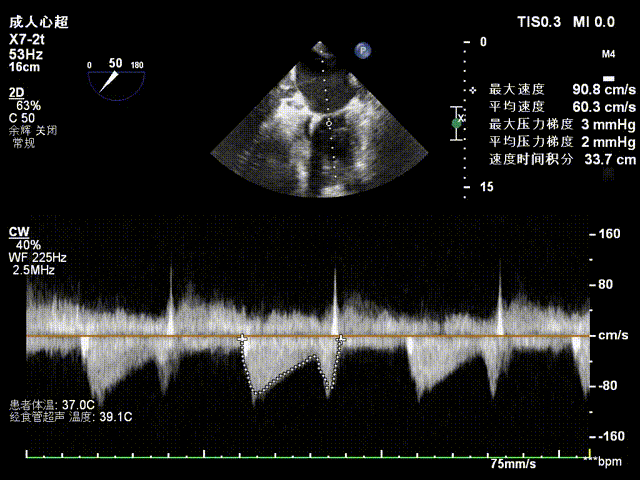

检查示组织桥明显,夹合器稳定,残余反流明显减少,降低至1+等级,二尖瓣平均跨瓣压差为3mmHg,经团队评估,手术效果达既定预期,各项指标平稳,顺利结束手术。

术后压差评估